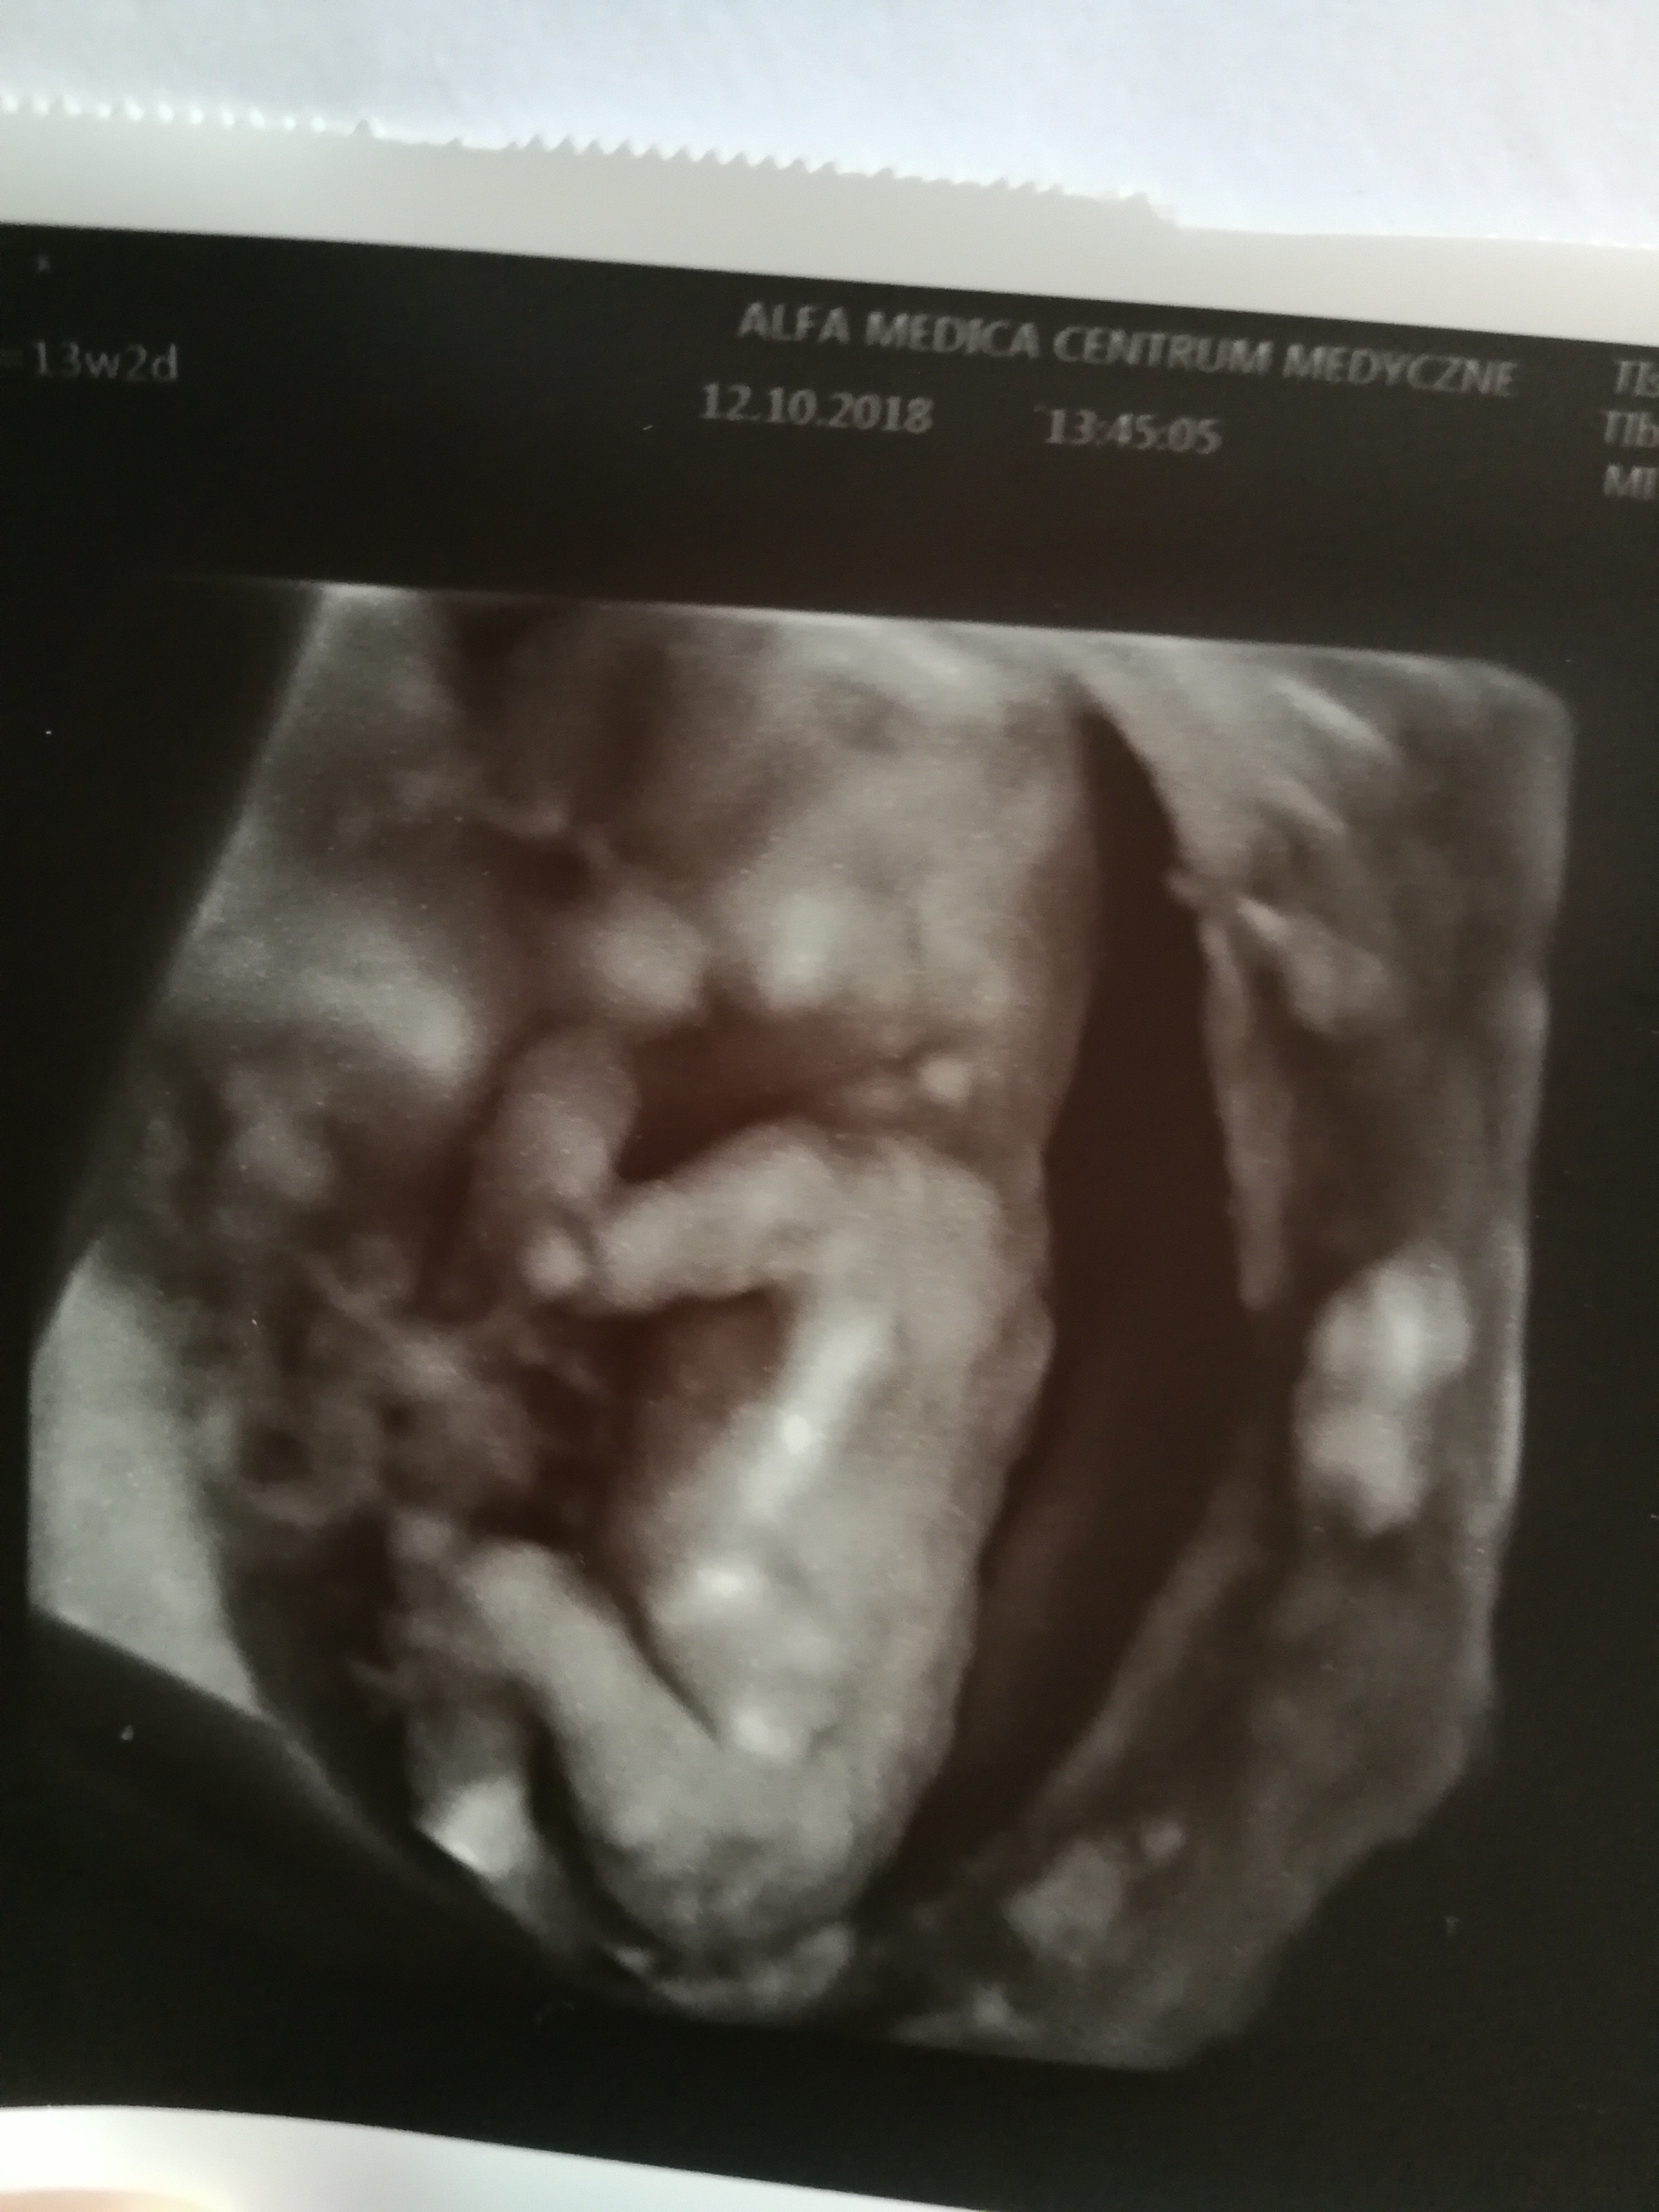

Uffff, wkońcu jesteśmy po prenatalnych ! według usg wszystko jest na miejscu prawidłowe, według om 13+2, według usg zawszę jest bobo większy 13+6. Doktor pobrał krew na papp-a i bete, za tydzień wyniki. Dzieciątko było cały czas przytulone do mojego brzuszka, cieżko było zobaczyć bezpośrednio co chowa między nogami, ale lekarz się swoim sposobem po wyrostku stwierdzil, ze jest on prostopadły, wiec na 80% chłopiec (ale za miesiąc mi dokładnie potwierdzi). Moja intuicja zawiodła.. Czułam dziewczynkę , ale tatuś zadowolony